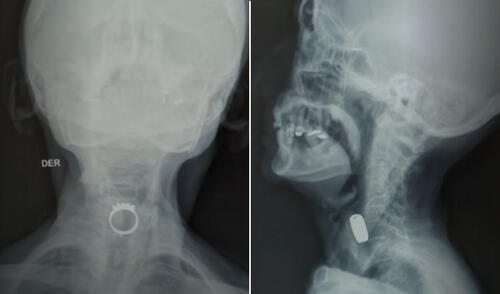

Al llegar al hospital, se realizaron los exámenes necesarios para evaluar su condición. Debido a su avanzada edad y su delicado estado de salud, pues presenta una fractura de cadera, el equipo médico aguardaba la autorización de un cardiólogo para proceder con la cirugía. Afortunadamente, este inconveniente fue resuelto rápidamente, permitiendo que se llevara a cabo la endoscopia para retirar el anillo.